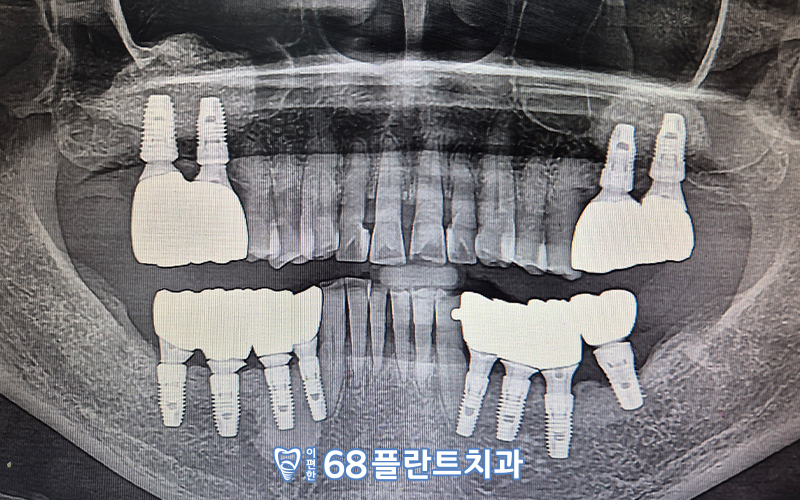

임플란트를 성공적으로 식립하였고

인공치근인 픽스처가

잇몸뼈에 잘 유착한것을 확인하고

크라운(보철물)을 올리는 작업을

진행해주었습니다.

타원에서 식립한 임플란트도

보철작업을 함께 잘 도와드렸답니다.